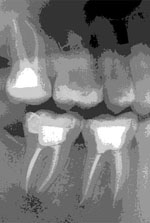

A gyökérkezelés célja a fertőzött szövetek eltávolítása a gyökércsatornából, belső tisztítás és a megfelelő hosszúságú és méretű üreg megformálása. Az így előkészített helyre a gyökértömő anyag behelyezhető, mely inertté teszi a fogat. Az érzéstelenítés után a kemény foganyagot átfúrva nyílást ejtünk az idegszál tetején a fogban, majd megfelelő méretű hozzáférést biztosítunk a gépi gyökérkezelő eszközök számára. A gyökércsatorna hosszának meghatározására elektromos hosszmeghatározási módszert alkalmazunk, bizonytalan esetben tűkontroll-felvételt készítünk. Az általunk használt gépi gyökérkezelő eszközök sokkal kónikusabbak, mint a hagyományos kézi eszközök, ezáltal nagyobb hatásfokú a tisztítás és nagyszámú beteganyagon értünk el hosszútávú sikereket. A csatornát vegyszerrel is átöblítjük, ami szintén a csírátlanítást szolgálja. Megfelelő méret elérése után paszta állagú és szilárd gyökértömő anyagot helyezünk a csatornákba, majd a fogat ideiglenes tömőanyaggal látjuk el a koronai részén.

Sajnos a már korábban gyökértömött fogak is fájhatnak (pl. helytelen munkahossz választás esetén, elnézett és nem kezelt csatorna, de lehet anatómiai akadály miatt is, mondjuk, ha a fő csatorna kettéágazik, stb.). Ez sok esetben a fog újra kigyökérkezelésével, a gyökértömés revíziójával helyrehozható. Ilyenkor a régi gyökértömés eltávolítása nehézkes lehet.